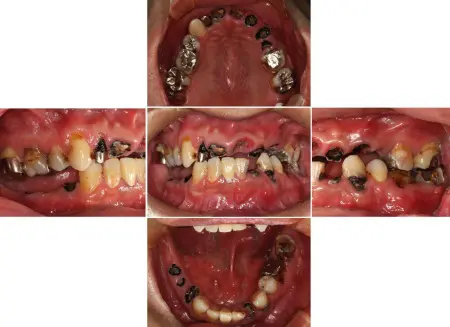

2024.12.1540代男性 天然歯をできる限り残すためにインプラントを用いながら虫歯の治療と噛み合わせを改善した症例